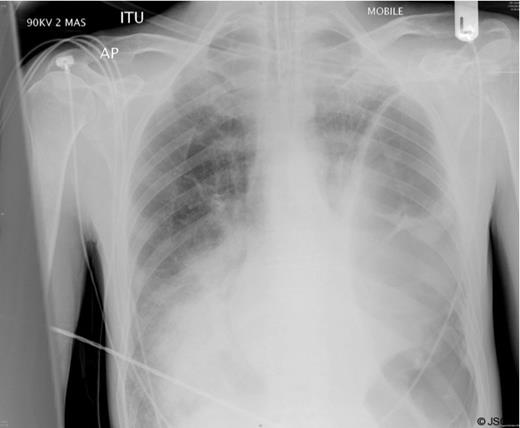

A chest radiograph (Figure 1) showed a large air filled structure within the left hemithorax, loss of clarity of the left hemidiaphragm and patchy consolidation of the middle and right lower lobes.

A clinical diagnosis of a possible spontaneous rupture of the diaphragm was made. The patient underwent an emergency laparotomy as he was not stable enough to undergo cross-sectional imaging to confirm the diagnosis. There were no abnormal findings at laparotomy. A left sided chest drain was immediately inserted with release of air under tension and pus (Figure 2).